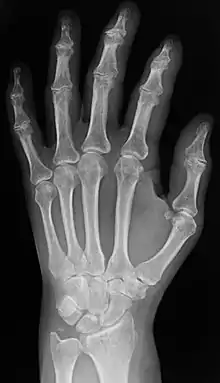

Plain x-ray of the wrist and hand

In the clinical context, "invisible light" medical imaging is generally equated to radiology or "clinical imaging". "Visible light" medical imaging involves digital video or still pictures that can be seen without special equipment. Dermatology and wound care are two modalities that use visible light imagery. Interpretation of medical images is generally undertaken by a physician specialising in radiology known as a radiologist; however, this may be undertaken by any healthcare professional who is trained and certified in radiological clinical evaluation. Increasingly interpretation is being undertaken by non-physicians, for example radiographers frequently train in interpretation as part of expanded practice. Diagnostic radiography designates the technical aspects of medical imaging and in particular the acquisition of medical images. The radiographer (also known as a radiologic technologist) is usually responsible for acquiring medical images of diagnostic quality; although other professionals may train in this area, notably some radiological interventions performed by radiologists are done so without a radiographer.

Radiography

Two forms of radiographic images are in use in medical imaging. Projection radiography and fluoroscopy, with the latter being useful for catheter guidance. These 2D techniques are still in wide use despite the advance of 3D tomography due to the low cost, high resolution, and depending on the application, lower radiation dosages with 2D technique. This imaging modality utilizes a wide beam of x rays for image acquisition and is the first imaging technique available in modern medicine.

• Projectional radiographs, more commonly known as x-rays, are often used to determine the type and extent of a fracture as well as for detecting pathological changes in the lungs. With the use of radio-opaque contrast media, such as barium, they can also be used to visualize the structure of the stomach and intestines – this can help diagnose ulcers or certain types of colon cancer.